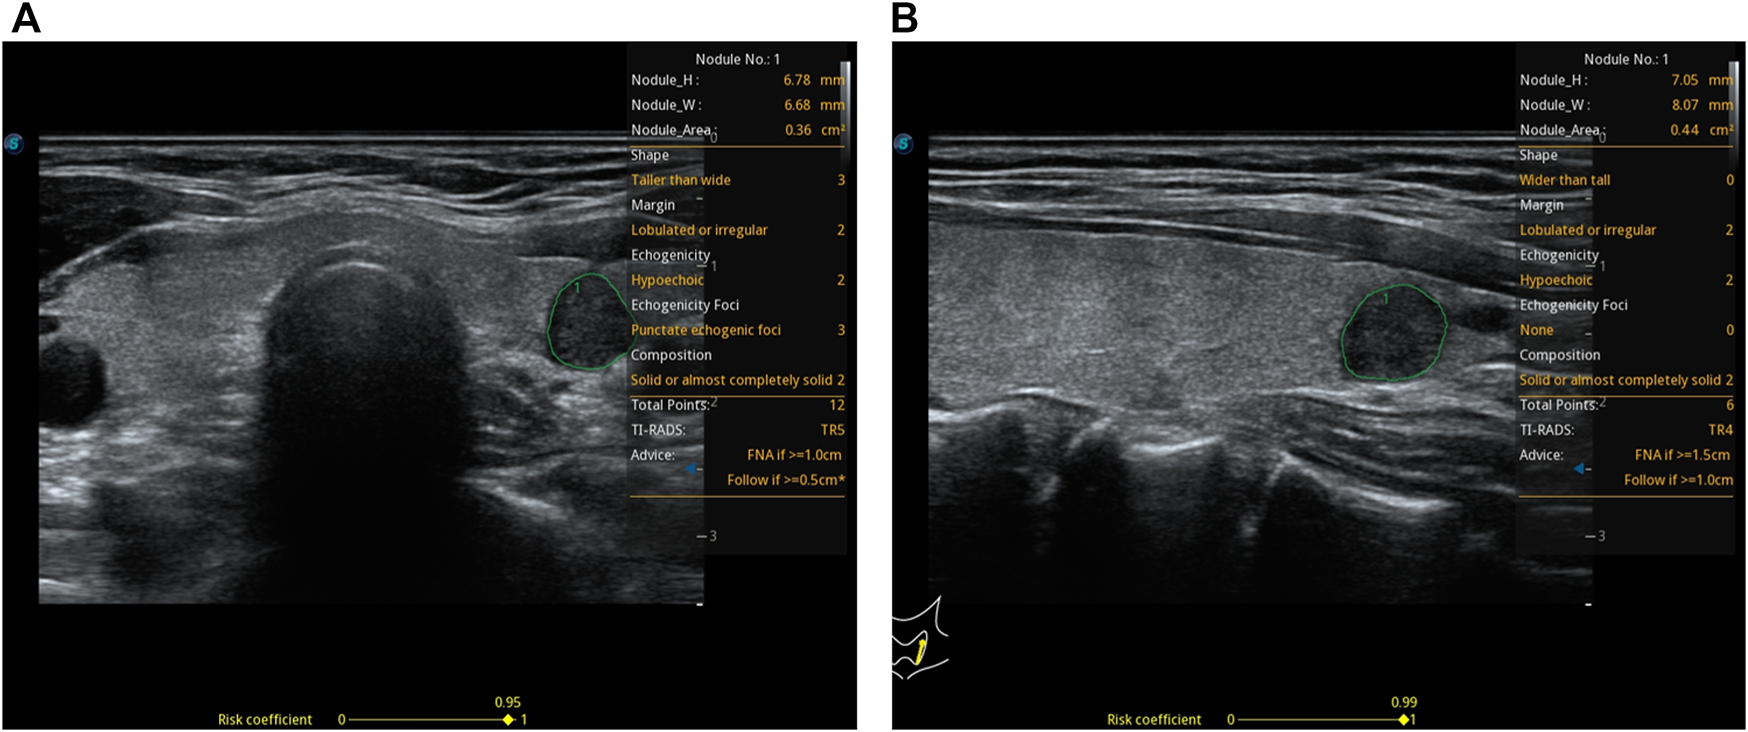

FIGURE 2

A 37-year-old woman with a thyroid nodule and pathological findings suggestive of a micro papillary thyroid carcinoma. S-thyroid analyzes the features of the lesion. (A) Transverse plane: shape = taller-than-wide; margin = lobulated or irregular; echogenicity = hypoechoic; echogenic foci = punctate echogenic foci; composition = solid or almost completely solid; TI-RADS classification = TR5; risk = 0.95. (B) Longitudinal plane: shape = wider-than-tall; margin = lobulated or irregular; echogenicity = hypoechoic; echogenic foci = none; composition = solid or almost completely solid; TI-RADS classification = TR4; risk = 0.99.